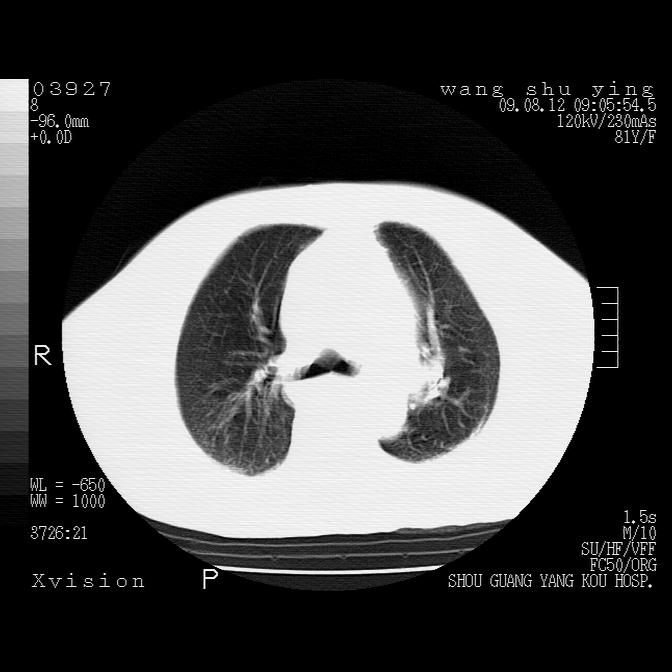

以下是引用帅河马在2009-8-12 12:59:00的发言:[br]两肺感染性病变伴双侧胸膜肥厚。[br]左侧甲状腺腺瘤不除外。[br]腹水+心包积液。[br][br][本贴已被 帅河马 于 2009-8-12 13:14:32 修改过]

以下是引用sdzyy在2009-8-12 18:17:00的发言:[br]两肺感染性病变伴双侧胸膜肥厚。[br]左侧甲状腺腺瘤不除外。[br]腹水+心包积液。[br]支持

以下是引用随光逐影在2009-8-12 19:42:00的发言:[br]1)两肺感染性病变伴双侧胸膜肥厚。2)不排除左侧甲状腺腺瘤。3)肝脏占位性病变;建议行进一步检查。